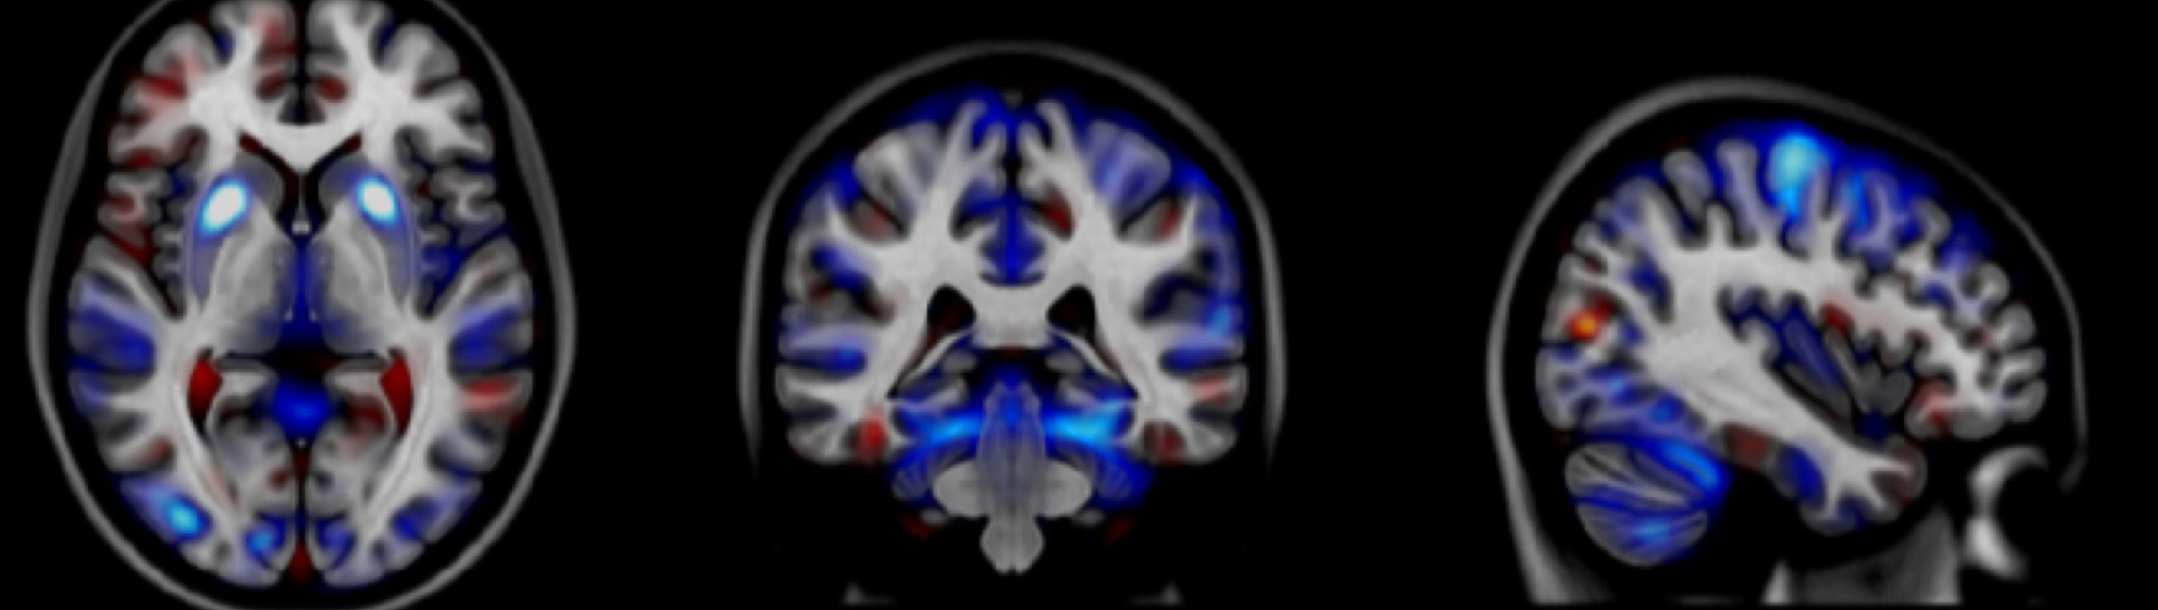

Our vision is that the MARC programme will develop the future UK clinical research leaders in addiction to build and sustain capacity in this vital area of clinical neuroscience and address the gap in clinical research capacity in the addictions field in the UK.

Addiction to alcohol, tobacco and drugs have a considerable economic and social impact on society in the UK and internationally. In addition concerns are growing about gambling, now classified as a behavioural addiction. Despite awareness of the magnitude of associated harms, the amount of evidence can be limited compared to other physical and mental health disorders.

Therefore opportunities of a career in clinical academic addiction are rarely presented with the result that there are very few existing potential candidates to become the future UK clinical research leaders in addiction. Consequently, there is a need to kick start clinical addiction research in order both to sustain capacity in this vital area of clinical neuroscience.